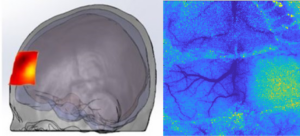

We explore new optical imaging methods mostly focused, but not limited, to measure and image cerebral perfusion in animals and humans.

• Laser Speckle Imaging

• functional Near Infrared Spectroscopy (fNIRS)